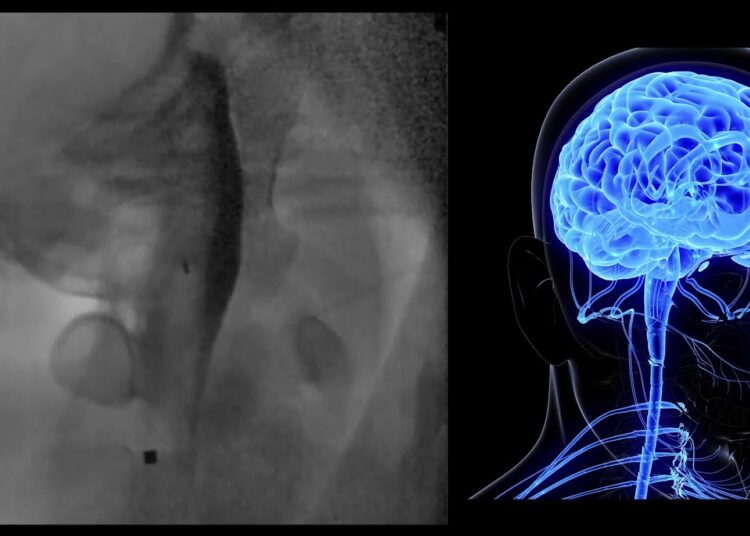

En una simulación realizada para mostrar la tecnología de este sistema, se vio cómo el robot seguía lentamente una trayectoria ya programada a través de un contenedor lleno de gel, que simulaba la densidad del cerebro humano.

Se vio cómo el robot, un cilindro metálico de pocos milímetros de largo, se acercaba a una bolsa llena de un líquido azul, que luego era perforada por el extremo puntiagudo del dispositivo a fin de que el líquido corriera.

De ese modo se probó cómo el robot podría usarse para perforar quistes llenos de fluidos dentro del cerebro cuando los ensayos clínicos inicien en dos años.